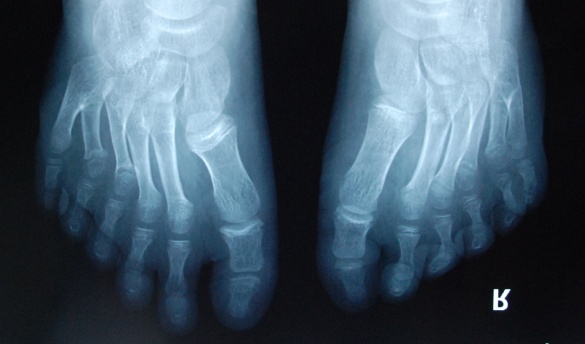

廈門眼科中心小兒眼科修陽暉博士在日常的診療過程中就接診了不少這樣的的特殊家庭,讓其尤為印象深刻的就是一年前接診的BBS綜合征患者。當時來院就診的是一對親兄弟,之前已在多家醫(yī)院做過檢查,因其均有較大散光和斜視,肉眼下眼底檢查未見異常,故外院均診斷為弱視,這也符合眼科門診常規(guī)的診斷邏輯與思維。但由于兄弟倆均有智力發(fā)育遲緩、特殊面容及四肢均有六指和六趾的特異體征引起了修陽暉博士的警覺:會不會是一種特殊遺傳性疾病或綜合征?后續(xù)的檢查結果進一步證實了修陽暉博士的懷疑---患兒均有夜盲,ERG、VEP及OCT檢查顯示雙眼的視網(wǎng)膜神經(jīng)上皮層結構及功能均明顯異常。由于之前未遇到此種病例,修陽暉博士在診斷一欄寫下視網(wǎng)膜色素變性并打上了個問號,同時留下了病人的聯(lián)系方式。

BBS綜合征(Bardet-Biedl綜合征)是一種主要累及纖毛結構與功能的罕見常染色體隱性遺傳性疾病。纖毛分布于哺乳動物體內的大多數(shù)細胞,它是一種廣泛存在于各種細胞表面的細胞器,體型微小但結構復雜、作用強大,能感知細胞外機械和化學信號變化并協(xié)助其轉導到細胞內部從而引起細胞應答。高等動物的視覺、觸覺、嗅覺、聽覺的傳遞都依賴于體內外正常的纖毛結構和功能。因此BBS綜合征常累及全身多個系統(tǒng)和器官,在臨床上主要表現(xiàn)為:視網(wǎng)膜色素變性、智力發(fā)育異常、向心性肥胖、多指(趾)、性腺發(fā)育異常、腎臟異常。除此之外還有許多諸如:語言發(fā)育障礙、聽力異常、嗅覺異常、斜視、白內障、散光、牙齒發(fā)育異常、短指(趾)、并指(趾)、肝纖維化、糖尿病、高血壓等表現(xiàn)。